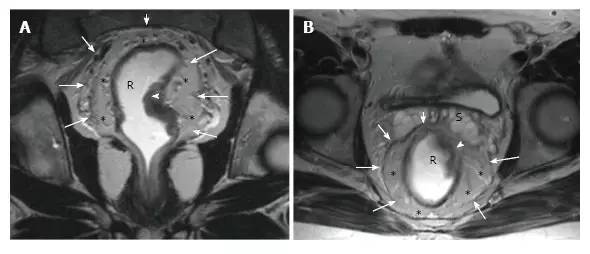

图 6. 直肠系膜和直肠系膜筋膜共振成像解剖学。在 T2 加权(A. 轴位和 B. 冠状位)磁共振图像上,直肠系膜筋膜(箭头)被看作是一个薄的低密度层,包围男性直肠癌患者的直肠系膜脂肪组织(*)和直肠。

图 13. EMVI。T2 加权(A)冠状和(B 和 C)连续轴向磁共振图像,在 T4a 直肠癌患者中显示不规则和扩大的血管信号插入肿瘤,与肿瘤有相同的信号强度(圆圈)。